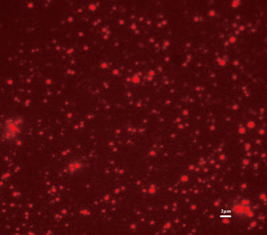

小鼠血液中分离纯化的,近红外荧光基因工程化细胞产生的,

近红外荧光蛋白标记的外泌体